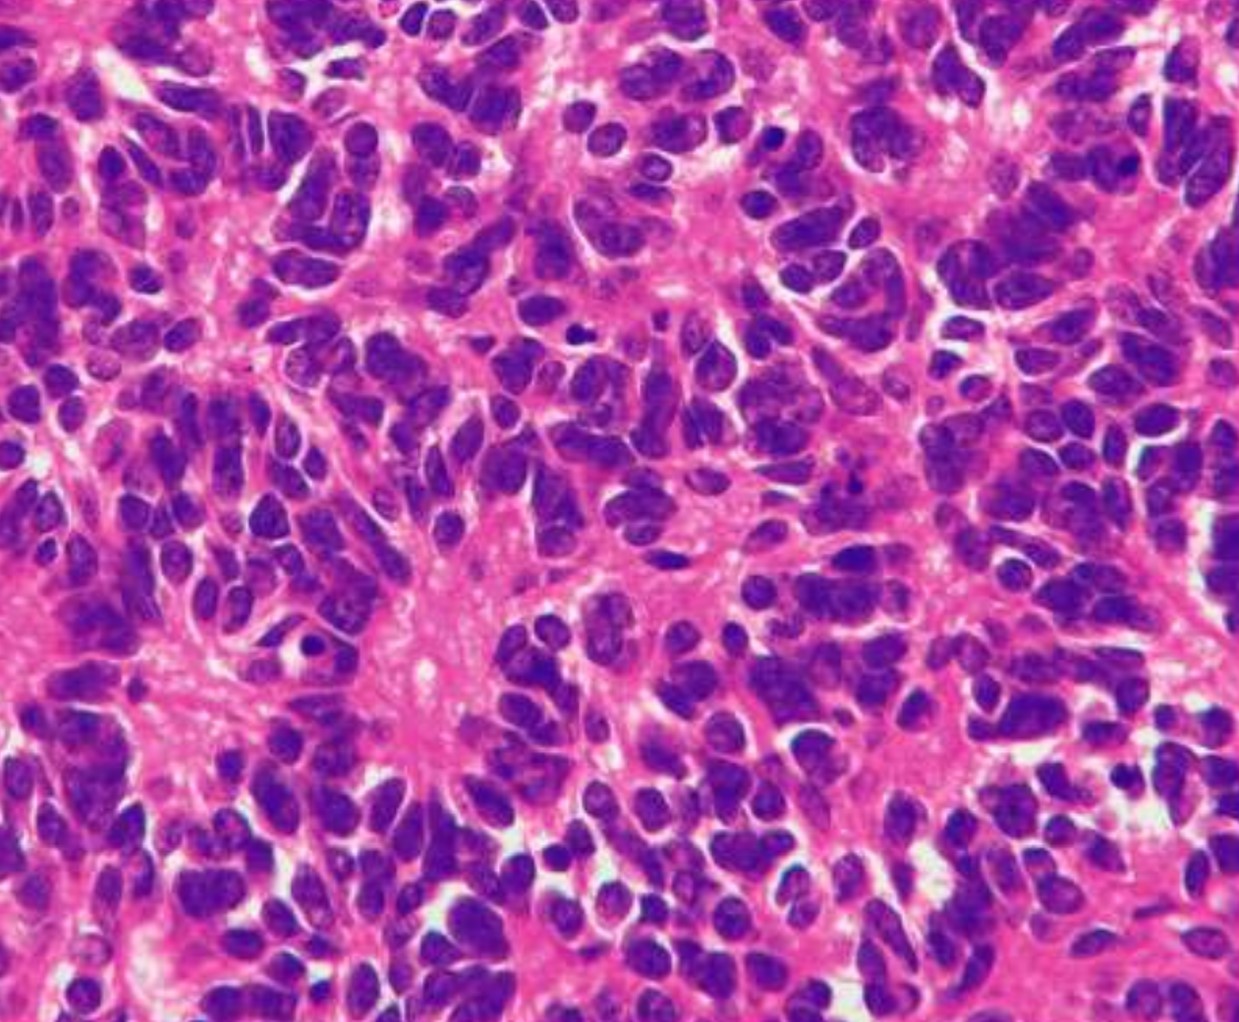

Medulloblastoma